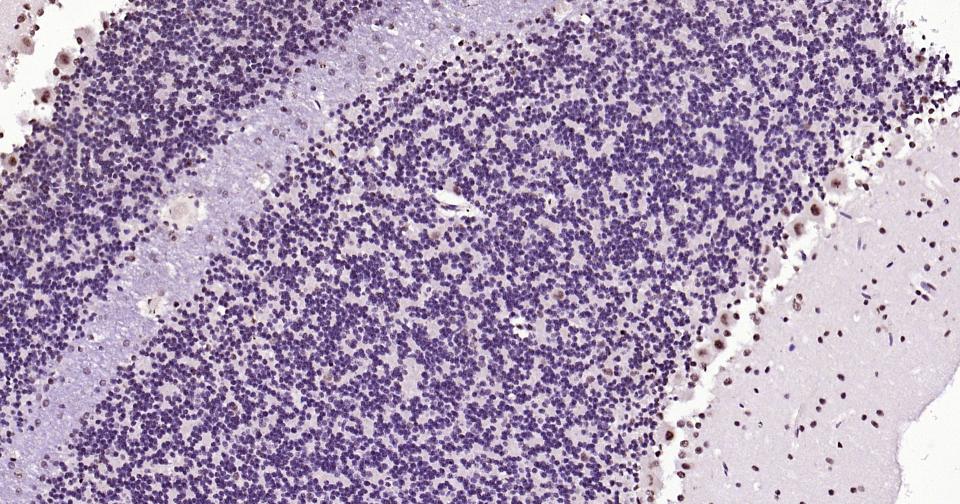

Paraformaldehyde-fixed, paraffin embedded Human Thyroid cancer; Antigen retrieval by boiling in sodium citrate buffer (pH6.0) for 15 min; Antibody incubation with Phospho-CREB-1 (Ser133) Monoclonal Antibody, Unconjugated(bsm-61105R) at 1:200 overnight at 4°C, followed by conjugation to the bs-0295G-HRP and DAB (C-0010) staining and DAB (C-0010) staining.